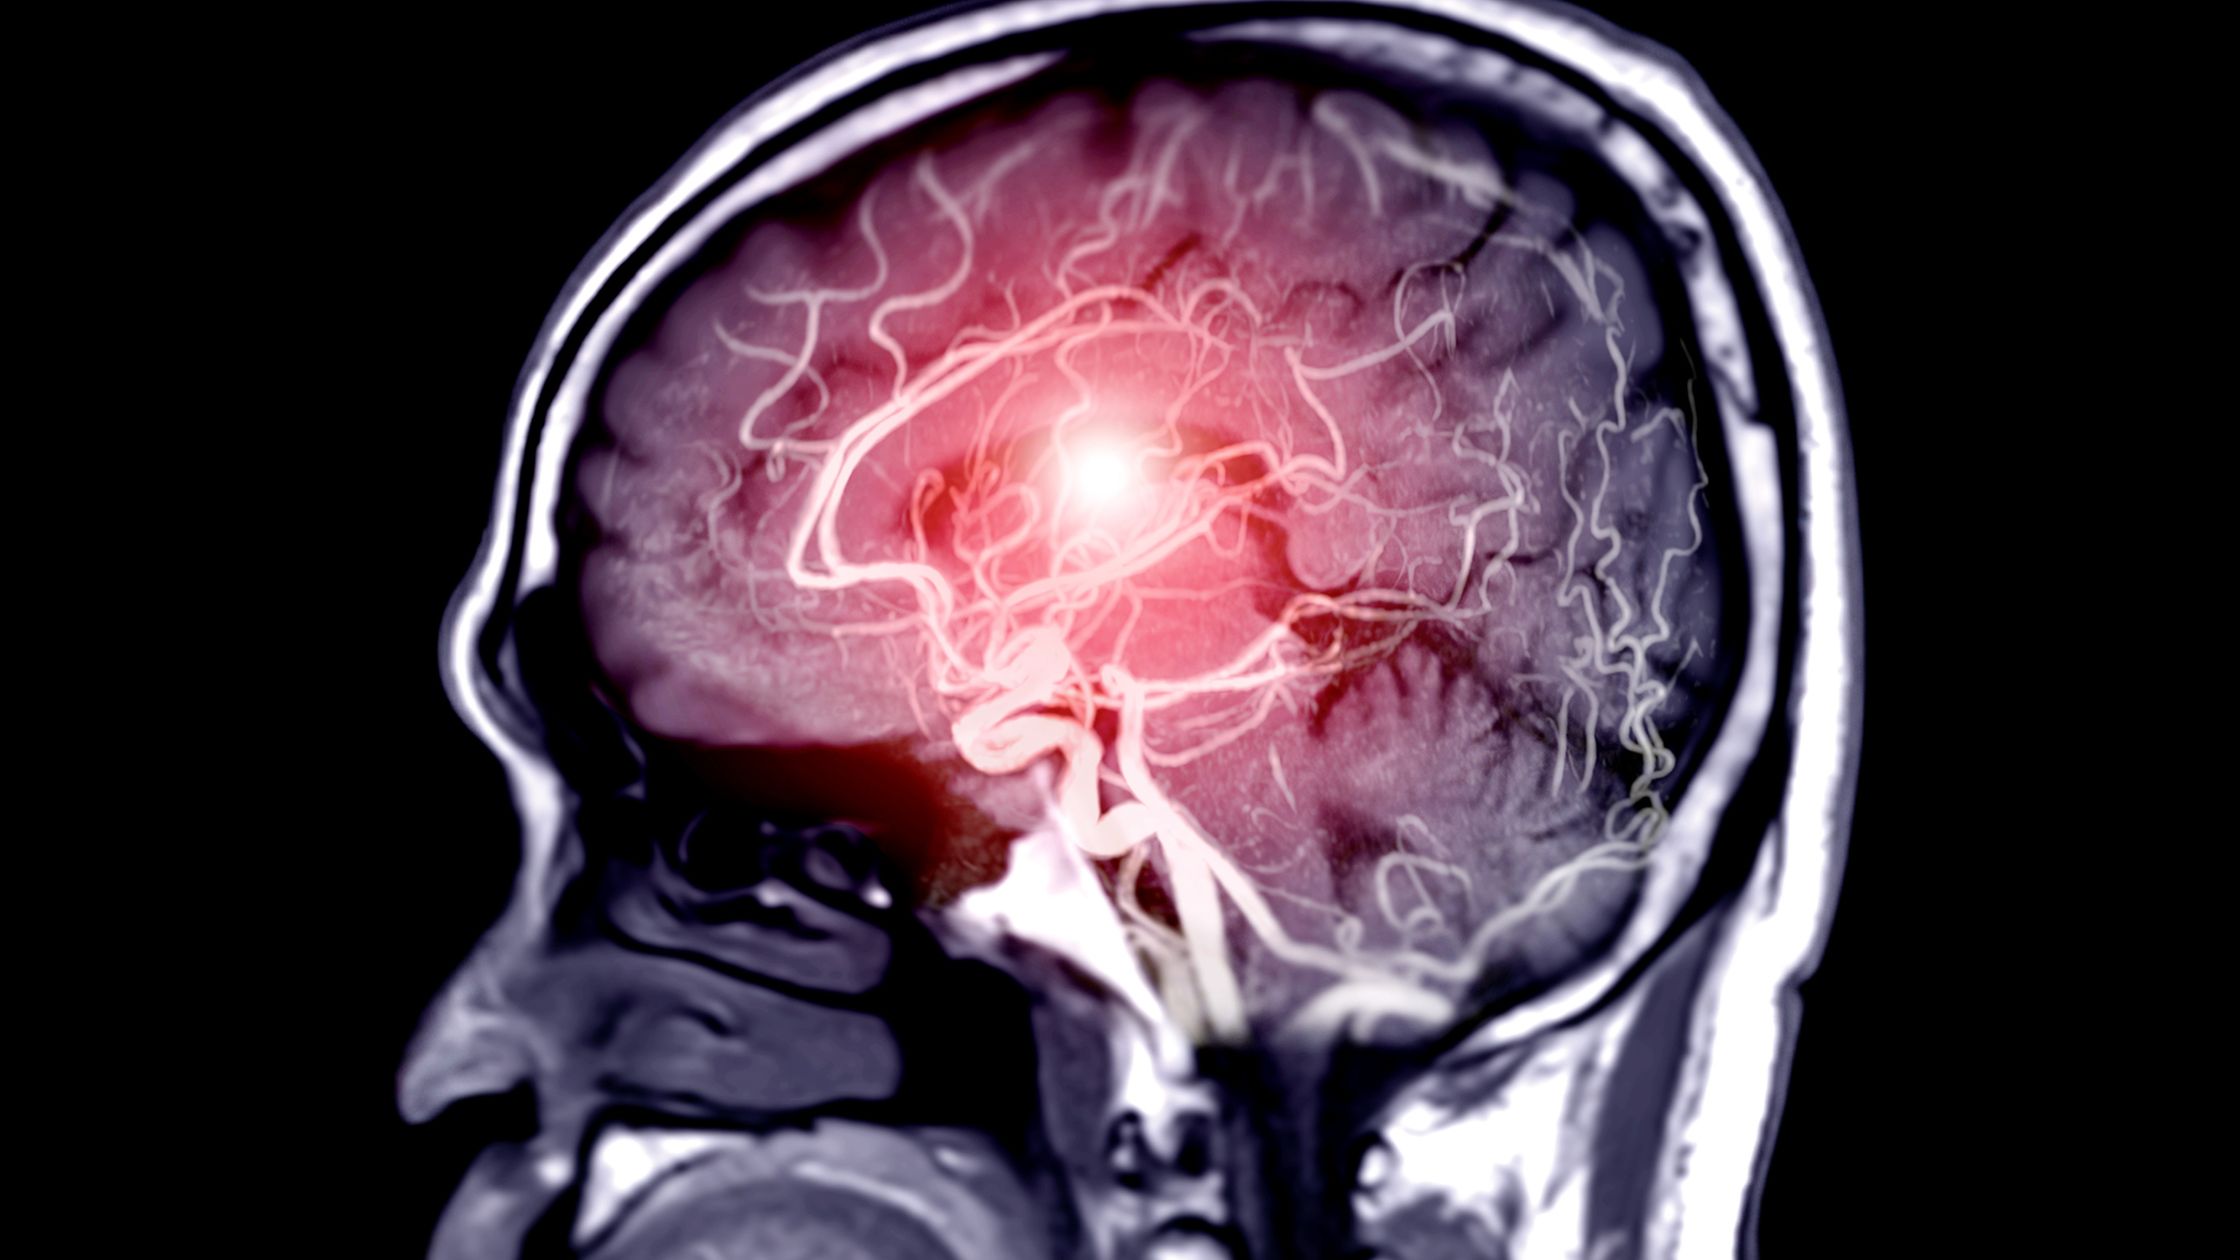

Infartos talámicos mediales bilaterales, un hallazgo típico debido a la oclusión de la arteria de Percheron